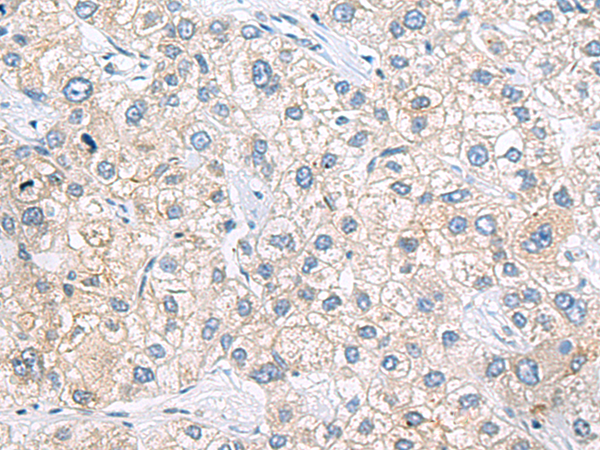

分类: 科研抗体货号: P12862别名: CGI-127应用: IHC反应种属: Human, Mouse